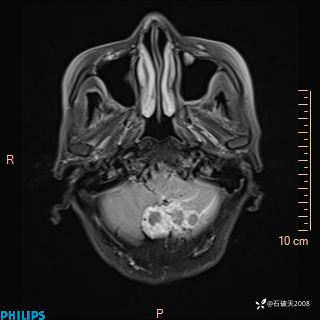

T2

T1

FLAIR